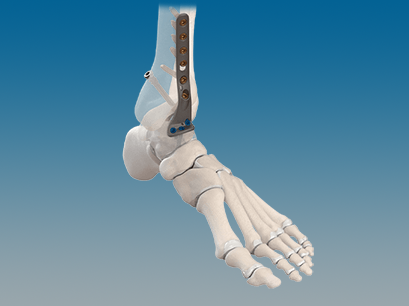

CONMED Foot and Ankle offers tailored innovation and simplified solutions. Explore our complete portfolio of arthroplasty, biologic, fixation, implant, suture anchor, and instrumentation offerings for foot and ankle surgery.